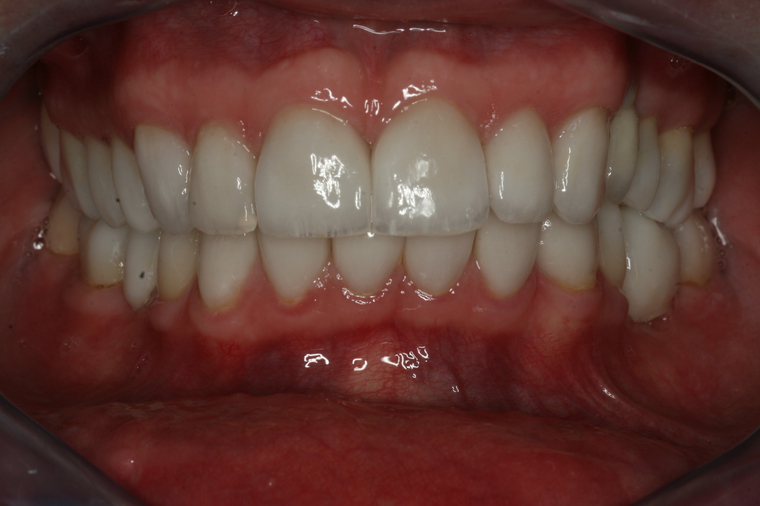

White-Is-Beautiful Konzept

- Beratung, Planung und Kostenaufstellung im ersten Termin

- Keine Wartezeiten, flexibles Zeitmanagement, Termine bis 21.00

und samstags möglich - Alle Behandlungsschritte aus einer Hand

- Eigenes Meisterlabor

- Sichere Amalgamentfernung

- Metallfreie biologische Materialien

- Schonende Behandlung in Vollnarkose

Bei einer Generalsanierung müssen alle zahnmedizinischen Bereich in Betracht gezogen werden, dies beginnt bei der Aufklärung und Prophylaxe, gefolgt von Zahnfleischbehandlungen und Kariestherapie, eventuellen Zahnentfernungen, Knochenaufbauten und wird durch ästhetischen Zahnersatz abgeschlossen. Unser Recall-System hält die erreichte Zahnsanierung über lange Jahre stabil.